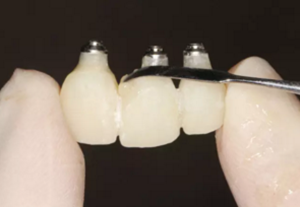

圖22 最終修復(fù)體

(4)最終修復(fù)。種植體周圍軟組織改建成熟以后,進(jìn)行最終修復(fù)。本 病例采用兩步法印模技術(shù)精確記錄種植體的三維位置和種植體周圍軟組織穿 齦輪廓外形。 首先,口內(nèi)制取臨時冠及周圍軟硬組織的硅橡膠陰模,復(fù)制軟硬組織 表面形態(tài)。然后,取下臨時修復(fù)體,常規(guī)制取閉窗式種植體水平聚醚印模, 精確記錄種植體的三維位置,灌制含人工牙齦的超硬石膏模型。最后,去除 模型上的人工牙齦,將臨時修復(fù)體戴入到模型上,在臨時修復(fù)體周圍和硅橡 膠陰模內(nèi)注入人工牙齦,將陰模就位到含臨時冠的石膏模型上,精確轉(zhuǎn)移穿齦輪廓外形,獲得工作模型。 制作螺絲固位的一體化氧化鋯基臺冠,以切削方式制作完成后,表面 添加飾瓷來獲得理想的美觀效果。 術(shù)后7個月,戴入最終修復(fù)體,紅白美學(xué)效果滿意。

(5)復(fù)查。種植體周圍骨水平穩(wěn)定,齦乳頭及齦高點(diǎn)位置穩(wěn)定,齦緣 曲線形態(tài)理想,唇側(cè)軟硬輪廓良好,功能滿意,修復(fù)效果符合預(yù)期。